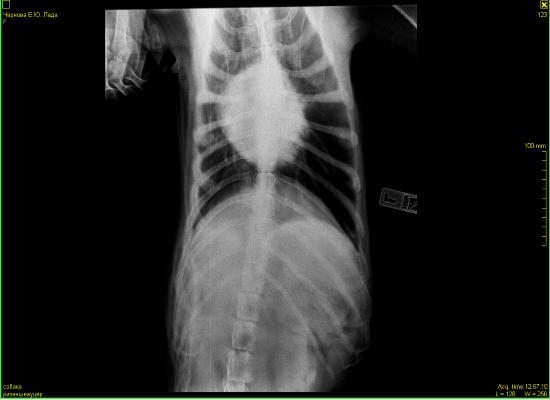

Всем доброго дня.Наши последние сводки с фронтов.В субботу мы сделали рентген.В программе,когда врач нам объяснял ситуацию,конечно было все более наглядно.Сейчас я не совсем понимаю,почему именно эти снимки открыты для доступа и почему именно их он записал.По словам врача у нас есть все ж изменения в области средостения в лимфаузлах. Что-то давит на пищевод.На снимке он должен быть прямой ,а он немного изогнут. Увеличено с одной стороны сердце и есть затемнения в легких справа(врач заметил именно затемнения,а не образования).По мне так совершенно ничего не понятно,а только больше вопросов возникло у меня.Нам назначили УЗИ и посещение кардиолога.Отсюда вопрос.Есть ли у кого ценный врач-кардиолог в районе СВАО? Операция по прежнему под ОЧЕНЬ большим вопросом.Лада пьет лекарства.Немного вялая от них.Гуляет ,кушает,спит и играет в мячик.Кашляет.

Прилагаю нашу добычу.

В легких безусловно что то есть.... вопрос что.

Сердце по рентгену не увеличено, у него " сглажена талия", что может быть при перегрузке правого сердца, которое отвечает за легкие . Повышено внутрилегочное давление из за mts в лимфоузлах скорее всего корня легких. Возможно начинает скапливаться жидкость в перекарде, а может все вместе. Мы никак не сможем на все это повлиять. Для всего, что я описала нужно не просто увидите жидкость в перекарде, а померить давление на лёгочной артерии, доплер на узи аппарате нужен. В принципе, что хотели узнать - есть там что то или артефакт. Есть(((. Грядку оперировать? Считаю, что операция только усугубит страдания. Все таки я за антибиотик и дексаметазон, и посмотреть. Клинически может уменьшиться кашель.